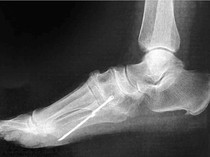

Foto Health Penampakan Batang Besi Nancap di Kaki Pasien, Baru Ketahuan Setelah 40 Tahun 8 jam yang lalu